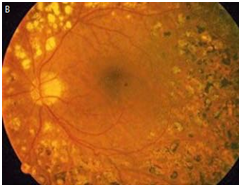

According to Table 2 LogMAR changed from the baseline 0.60 LogMAR (20/80) in the of Bevacizumab group and 0.50 LogMAR (20/60) in the PRP group, to 0.40 LogMAR (20/50) in the Bevacizumab group and 0.50 LogMAR (20/60) in the PRP group at week 52 (P=0.14) (Figure 1). At 52 weeks intravitreal Bevacizumab was non-inferior to PRP interim of visual acuity, and there is no significant change in visual acuity, BCVA was converted from Snellen to LogMAR for statistical analysis. As shown in Table 2 central retinal thickness changes at 52 weeks from baseline -48 (-62 to -32) in the Bevacizumab group and -16 (-21 to -8) in the PRP group (p<0.001) however the probability of developing DME was higher in the PRP group, due to the small group of patients, and the randomization” where DME patients exceeds PRP patients”; we can’t have a firm conclusion. The improvement of diabetic retinopathy at 52 weeks was 11 eyes without PDR, 3 eyes with regressed neovascularization, 2 eyes with active neovascularization and 9 eyes improved two steps in DR severity in Bevacizumab group (Figure 2) where 4 eyes without PDR, 9 eyes with regressed neovascularization, and 1 eye with active neovascularization in PRP group (p=0.43) where the two steps improvement in DR severity was non assessable in the PRP group (Figure 3). No systemic nor ophthalmic events where noted in both arms of the study except of one patient in the Bevacizumab groups developed hyphema and vitreous hemorrhage the next day after injection and was treated mydriatic and topical steroids which hemorrhage has resolved without any ocular or retinal damage then scheduled for PRP.

Figure 3 A shows a patient with PDR, baseline BCVA is 20/63; B shows same patient after 52 weeks Panretinal photocoagulation (PRP), BCVA 20/32.